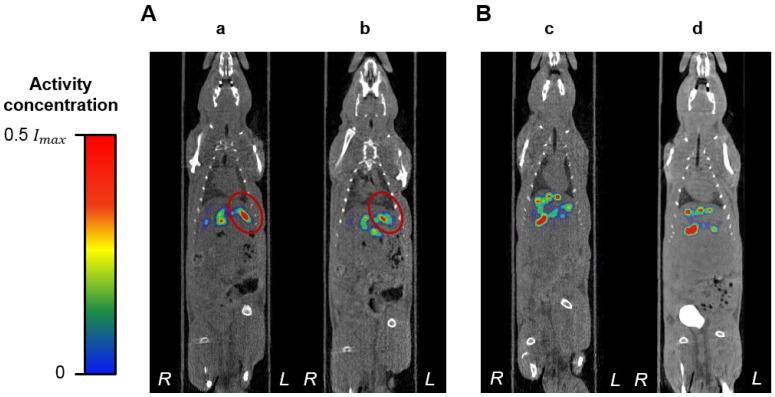

A common form of treatment for patients with hepatocellular carcinoma (HCC) is transarterial radioembolization (TARE) with non-degradable glass or resin microspheres (MS) labeled with Y (Y-MS). To further simplify the dosimetry calculations in the clinical setting, to have more control over the particle size and to change the permanent embolization to a temporary one, we developed uniformly-sized, biodegradable Re-labeled MS (Re-MS) as a new and easily imageable TARE agent. MS made of poly(-lactic acid) were produced in a flow focusing microchip. The MS were labeled with Re using a customized kit. An orthotopic HCC animal model was developed in male Sprague Dawley rats by injecting N1-S1 cells directly into the liver using ultrasound guidance. A suspension of Re-MS was administered via hepatic intra-arterial catheterization 2 weeks post-inoculation of the N1-S1 cells. The rats were imaged by SPECT 1, 24, 48, and 72 h post-radioembolization. The spherical Re-MS had a diameter of 41.8 ± 6.0 µm ( = 14.5%). The site and the depth of the injection of N1-S1 cells were controlled by visualization of the liver in sonograms. Single 0.5 g tumors were grown in all rats. Re-MS accumulated in the liver with no deposition in the lungs. Re decays to stable Os by emission of β particles with similar energy to those emitted by Y while simultaneously emitting γ photons, which were imaged directly by single photon computed tomography (SPECT). Using Monte Carlo methods, the dose to the tumors was calculated to be 3-6 times larger than to the healthy liver tissue. Re-MS have the potential to become the next generation of β-emitting MS for TARE. Future work revolves around the investigation of the therapeutic potential of Re-MS in a large-scale, long-term preclinical study as well as the evaluation of the clinical outcomes of using Re-MS with different sizes, from 20 to 50 µm.

一种治疗肝细胞癌 (HCC) 患者的常用方法是经动脉放射性栓塞术 (TARE),使用不可降解的玻璃或树脂微球 (MS) 标记钇 (Y-MS)。为了进一步简化临床实践中的剂量计算,更好地控制粒径,并将永久性栓塞转变为暂时性栓塞,我们开发了具有均匀尺寸的可生物降解的放射性标记 MS (Re-MS),作为一种新型且易于成像的 TARE 试剂。聚乳酸 (poly(-lactic acid)) 制成的 MS 在流聚焦微芯片中生产。使用定制试剂盒对 MS 进行放射性标记。通过超声引导将 N1-S1 细胞直接注射到肝脏中,在雄性 Sprague Dawley 大鼠中建立了原位 HCC 动物模型。在接种 N1-S1 细胞后 2 周,通过肝内动脉导管术给予 Re-MS 混悬液。在放射性栓塞后 1、24、48 和 72 h 进行 SPECT 成像。球形 Re-MS 的直径为 41.8 ± 6.0 µm (=14.5%)。通过 sonogram 中肝脏的可视化来控制 N1-S1 细胞注射的部位和深度。所有大鼠均成功生长出单个 0.5 g 的肿瘤。Re-MS 积聚在肝脏中,而不在肺部沉积。Re 通过发射与 Y 相同能量的β粒子衰变为稳定的 Os,同时发射γ光子,可直接通过单光子计算机断层扫描 (SPECT) 成像。使用蒙特卡罗方法计算,肿瘤的剂量比健康肝组织大 3-6 倍。Re-MS 有可能成为下一代用于 TARE 的β发射 MS。未来的工作将围绕大规模、长期的临床前研究来评估 Re-MS 的治疗潜力以及使用不同尺寸(20-50 µm)的 Re-MS 的临床结果进行。